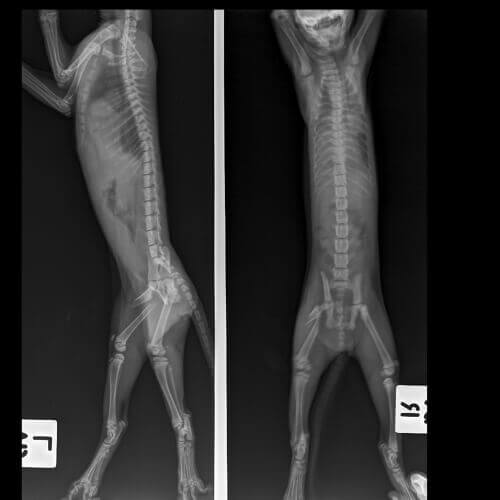

Lameness in cats and diagnosis

It’s important to point out the importance of getting a proper diagnosis so that your cat doesn’t end up with permanent muscular or nervous disorders. Your vet will carry out a complete examination of your cat to try to determine the precise cause of the problem.

Your cat’s age, injury history, whether the problem is acute or chronic, the severity of their lameness, and how many legs are involved are all factors that can help point to the source of the problem.

The diagnosis may require some special tests which often involve one or more of the following:

- X-ray